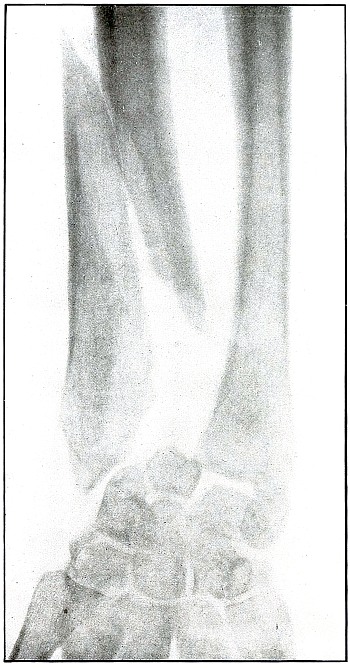

| 29. |

Gunshot fracture, radius, lower end |

68 |

| 30. |

Gunshot fracture, radius, lower end |

70 |

| 31. |

Gunshot fracture, radius, lower end |

72 |

| 32. |